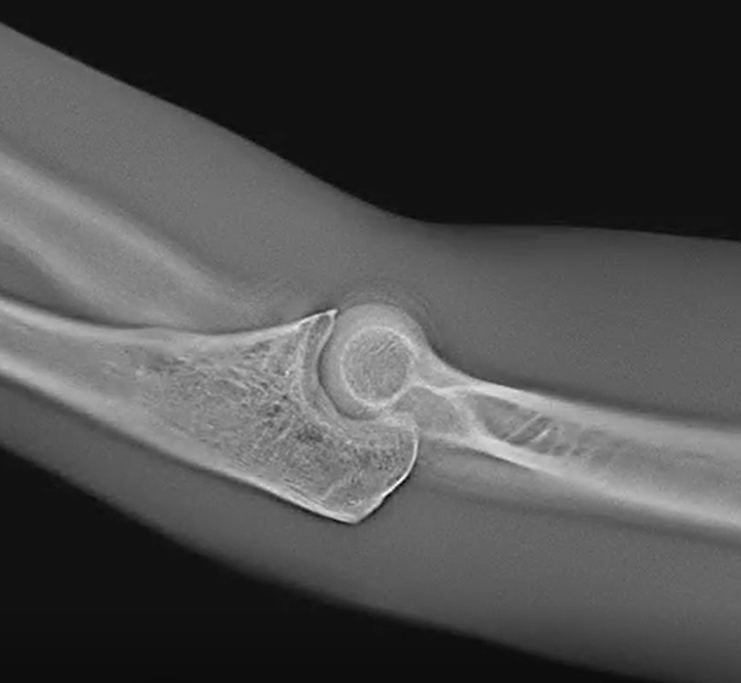

Sharper 3D Insights.

Previous DT had limited depth resolution which could lead to difficulties in localizing some structures. However, the Adaptix DT 3D technology ‘sweeps’ in two dimensions, enhancing ‘z’ resolution relative to conventional DT.